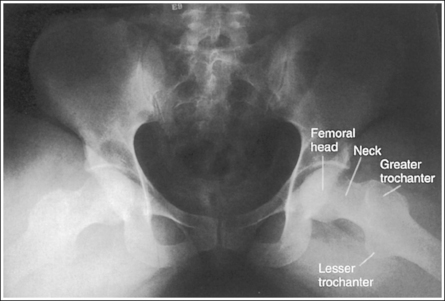

Hip: Anteroposterior Projection

• An AP projection of the hip is obtained by placing the patient supine on the imaging table with the legs extended (Figure 7-3). To ensure that the pelvis is not rotated, judge the distances from the anterior superior iliac spines (ASISs) to the imaging table. The distances on each side should be equal.

The femoral neck is demonstrated without foreshortening, the greater trochanter is in profile laterally, and the lesser trochanter is superimposed by the femoral neck.

• Accurate leg positioning. To demonstrate an AP hip projection with the femoral neck shown without foreshortening and the greater trochanter in profile, the patient's leg should be internally rotated until the foot is angled 15 to 20 degrees from vertical and the femoral epicondyles are positioned parallel with the imaging table (Figure 7-4; see Figure 7-1). A sandbag or tape may be needed to help the patient maintain this internal leg rotation.

The femoral head or neck is at the center of the exposure field. The acetabulum, greater and lesser trochanters, femoral head and neck, and half of the sacrum, coccyx, and symphysis pubis are included within the collimated field. Any orthopedic apparatus located at the hip are included in their entirety.

• A perpendicular central ray is centered 1.5 inches (4 cm) distal to the midpoint of a line connecting the ASIS and superior symphysis pubis, to center the hip joint in the center of the exposure field, and a perpendicular central ray is centered 2.5 inches (6.25 cm) distal to the midpoint of a line connecting the ASIS and superior symphysis pubis to place the femoral neck in the center of the exposure field (Figure 7-6). Center the IR to the central ray and open the longitudinal collimation enough to include the ASIS and any hip orthopedic apparatus. Transversely collimate to the patient's midsagittal plane and within 0.5 inch (1.25 cm) of the lateral hip skin line. Including half of the sacrum, coccyx, and symphysis pubis within the exposure field provides a way to evaluate pelvic rotation.